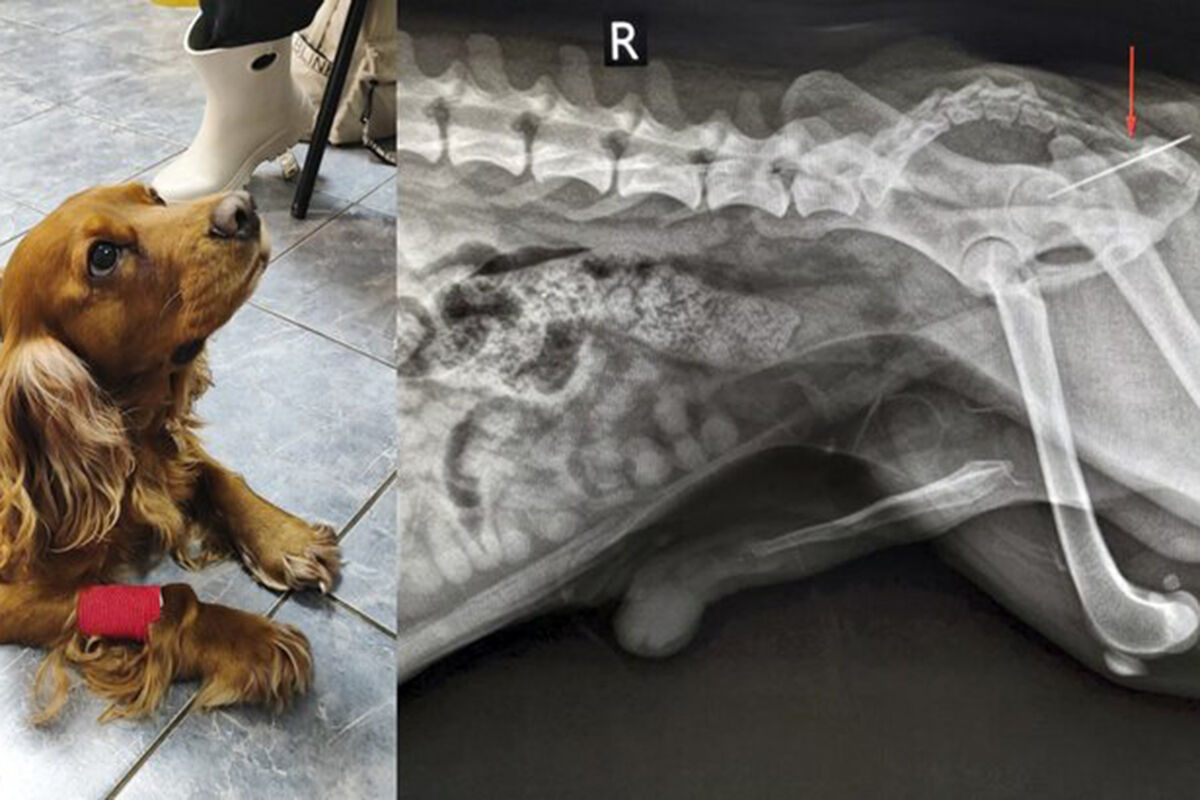

В ветклинике Коптево специалисты спасли собаку породы кокер-спаниель по кличке Вольт, которая проглотила швейную иглу. Об этом »Москве 24» рассказали в столичной госветслужбе.

«При осмотре терапевт Анна Кубатина заметила, что из заднего прохода Вольта торчит швейная нитка. Пациента срочно отправили на рентген», – добавили в пресс-службе.

Врачи установили, что за ниткой тянулась и игла, которая застряла в прямой кишке. Хирург Евгений Бахтин и анестезиолог Светлана Дорожкина провели операцию по извлечению иглы, после этого питомца отпустили домой.